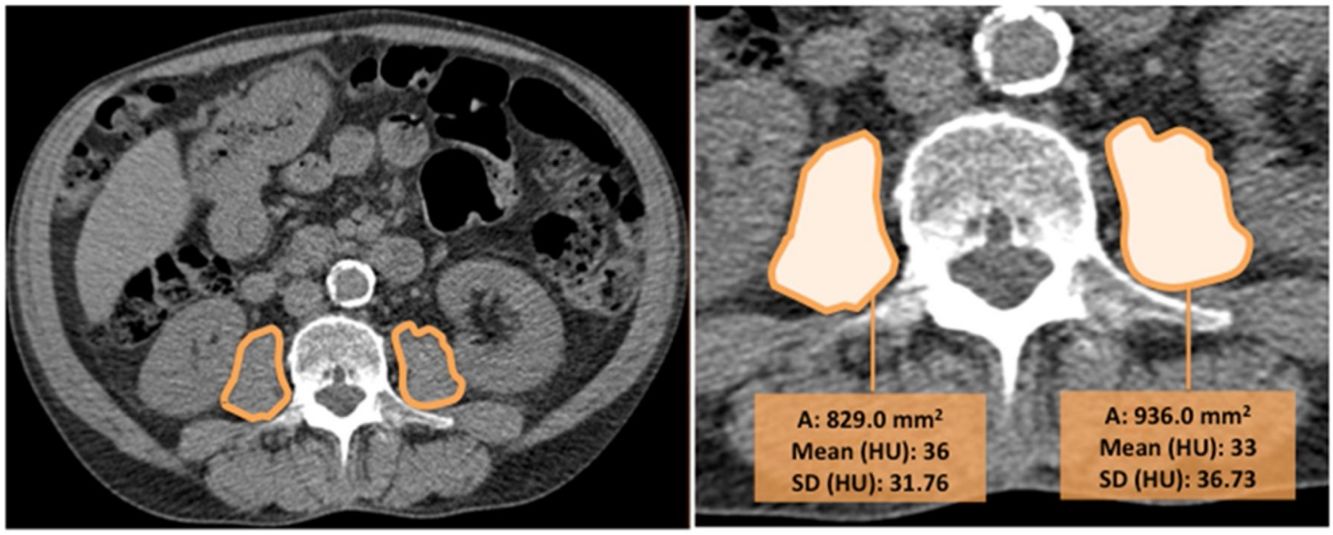

CT images were used to determine the psoas muscle cross-sectional area and density, an indirect estimation of muscle quality. Two independent radiologists blinded to patients’ clinical data and to the outcome, measured the right and left psoas muscles at the level of the third lumbar vertebra on axial CT images (we selected the slice that was in the middle of the vertebra, equidistant from the superior and inferior border). The imaging analysis was performed in one centre to ensure homogeneity in the reading and the interobserver agreement was excellent (k=0.82). Right and left psoas muscle cross-sectional areas (cm2) (RPsA and LPsA, respectively) were employed to obtain the total psoas area (TPsA; TPsA=RPsA+LPsA). In addition, mean attenuation values in Hounsfield unit (HU) and its standard deviations (SD) were also registered (Fig. 1).

The values obtained were used to measure psoas density.15,17,19 Psoas muscle density, was estimated adding the product of the right mean psoas HU density and RPsA with that of the product of the left mean psoas HU density and LPsA, then dividing by the TPsA19: PsD=[(right psoas attenuation*right PsA)+(left psoas attenuation*left PsA)]/TPsA. Psoas index (PsI) was also calculated computing psoas muscle areas and normalising by the height squared: PsI=TPsA/height2.